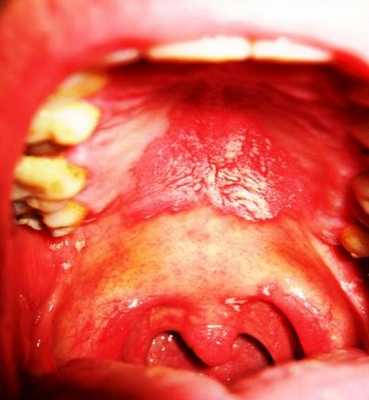

Наиболее частое заболевание при ВИЧ-инфекции – кандидоз носоглотки, наружного уха. Обычно они проявляются зудом в ухе, формированием ангулита, выделением бело-серых масс творожистой консистенции с неприятным запахом, иногда – с примесью крови, кондуктивной тугоухостью, выраженным увеличением шейных, поднижнечелюстных лимфоузлов, нарастанием общей интоксикации организма. Патологические изменения ЛОР-органов при гистоплазмозе включают в себя глубокие эрозии в носоглотке, ротоглотке и на небе, сопровождающиеся выраженной болью при глотании. Реже язвы формируются на коже наружного носа или ушей. Визуально они имеют бугристую поверхность с приподнятыми краями. Местные проявления сочетаются с резким повышением температуры до 39,0-40,5° C, признаками поражения легких, печени, селезенки.

У больных СПИДом встречается заболевание, которое называют «волосатой лейкоплакией». Оно представляет собой утолщение слизистой оболочки, которое имеет белый цвет и сморщенную неровную поверхность. Локализуется по краю языка и на слизистой оболочке щек. Вызывается папилломавирусом или вирусом Эпштейна-Бара.